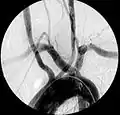

Images

Aberrant right subclavian artery at angiography.